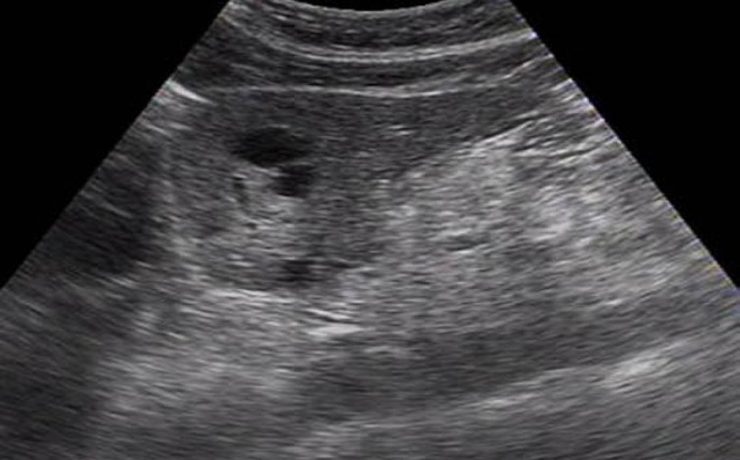

Aspectos ultrasonograficos del riñón

Los riñones órgano parque se encuentra en ambos lado de la columna vertebral dorso-lumbar, se sobreponen parcialmente en la parrilla costal baja y se sitúan retroperitoneales entra la 3ra y 6ta vertebra lumbares. Se dividen para su estudio en corteza, medula y seno; La densidad de su parénquima (medula y